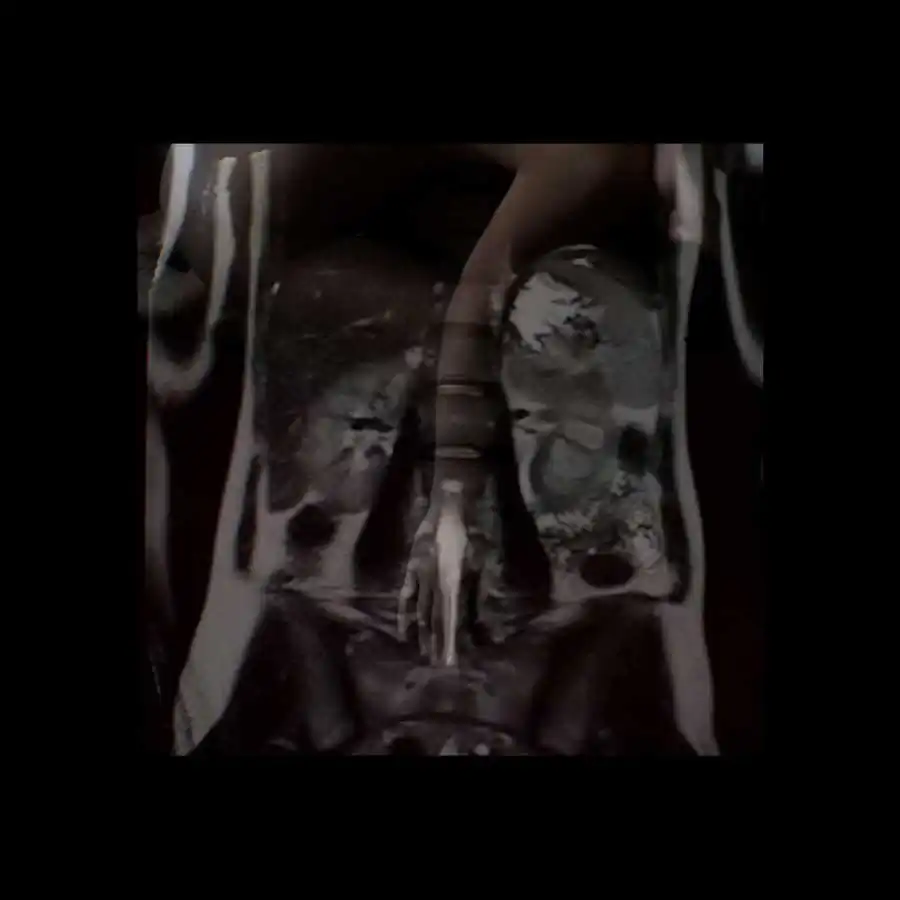

The project ‘Limits of existence’ are self-portraits compiled by the author with MRI scans. It is a case-record, in which the body appears as a subject to internal researches and the only way of communication with the outside world.

Working with the fear of physical existence termination, the author examines the physiological processes that occur during her illness with the threat of death, as the only real manifestation of life, as the limits of the possible. All thoughts, feelings and experiences, focused on physical sensations, force the author to reconsider the meaning of ‘Me’, ‘person’, ‘soul’; also the question of possibility for the spirit to overcome the boundaries of the body or expand them is raised. [Official Website]